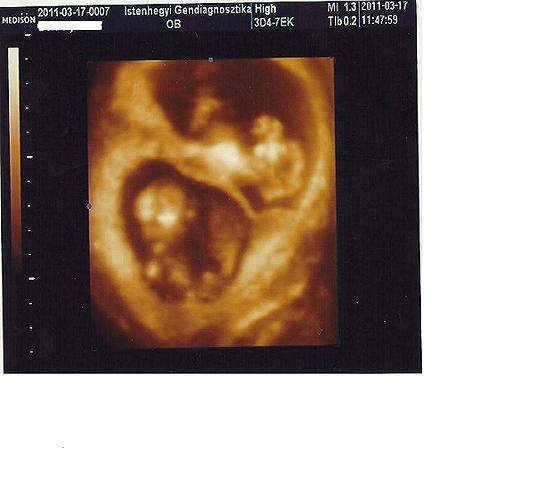

nekünk tegnap a flowmetria eredményünk lett rossz, ezért kellett átmennem a Jánosba, ott is elég rosszul indult a ctg, de aztán jó lett és csináltak még ott is egy flowmetriát, az már rendben volt.

a mai ctg jó lett, így val.szeg a kisfiúnk "csak" ránk ijesztett. de a szülőszobás pakkom legalább össze lett készítve!